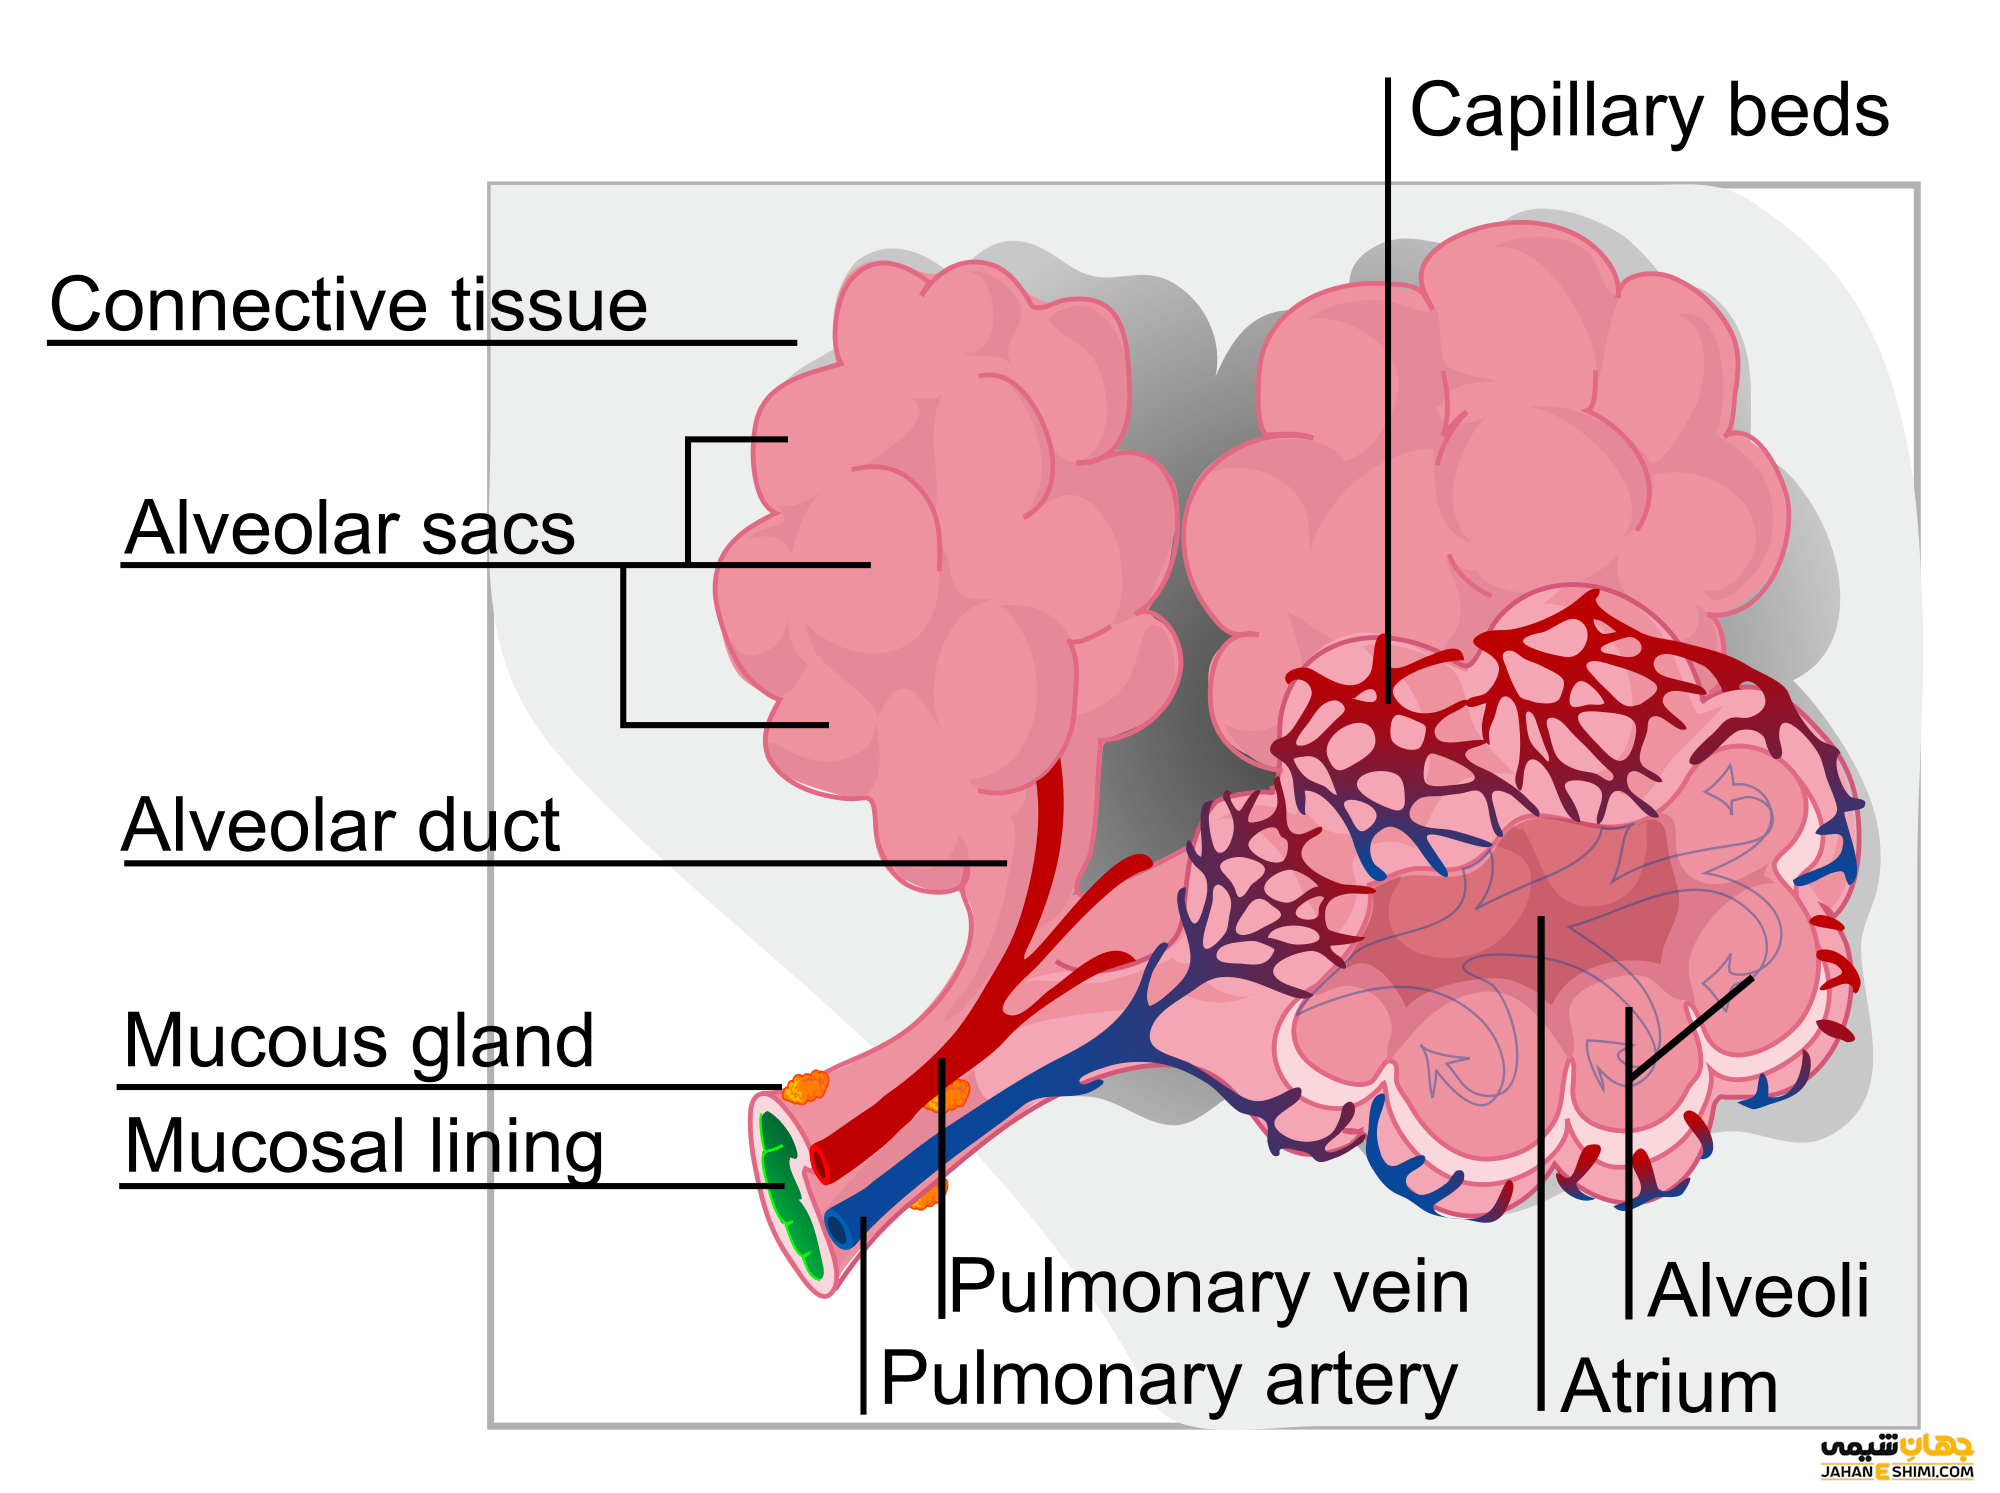

درخت برونشیال مجموعه ای از راه ها است که هوا را به آلوئول های ریه می رساند. این قسمت از نای شروع می شود و به برونش چپ و راست تقسیم می شود.

هر برونش با عبور از هیلوم وارد ریشه ریه می شود. در داخل ریه ، آنها تقسیم می شوند و برونش های لوبار را تشکیل می دهند که هر کدام هوای یک لوب را تأمین می کند.

سپس هر برونش لوبار به چندین برونش سگمنتال ۳ بخشی تقسیم می شود. هر برونش سگمنتال هوا را به بخش برونش ریوی می رساند که واحدهای عملکردی ریه ها هستند.

برونش های سگمنتال باعث ایجاد بسیاری از برونشیول های می شوند که در نهایت به برونشیول های انتهایی تبدیل می شوند. هر برونشیول انتهایی به برونشیول های تنفسی ختم می شود که دارای دیواره های نازک هستند که از لومن های آنها گسترش می یابد. اینها آلوئول هایی هستند که محل تبادل گاز هستند.

عروق ریه (شش)

ریه ها از طریق شریان های ریوی خون فاقد اکسیژن را دریافت می کنند. هنگامی که خون اکسیژن دریافت کرد ، از طریق چهار رگ ریوی از ریه ها خارج می شود (دو رگ برای هر ریه)

نایژه ها شبکه ای از لوله های شاخه ای هستند که هوا را به داخل ریه ها وارد و خارج می کنند. در انتهای کوچکترین شاخه های آنها دسته هایی از کیسه های هوای کوچک به نام آلوئول وجود دارد که هنگام استنشاق از هوا پر می شوند.

سیستم تنفسی شما از ریه ها، راه های هوایی (نای، برونش ها و برونشیول ها)، دیافراگم، جعبه صدا، گلو، بینی و دهان شما تشکیل شده است. وظیفه اصلی شش تنفس اکسیژن و بازدم دی اکسید کربن است. همچنین از شما در برابر ذرات و میکروب های مضر محافظت می کند و به شما امکان می دهد بو کنید و صحبت کنید. عملکرد اصلی شش ها این است که اکسیژن را برای سلول های بدنتان جذب کند و از شر دی اکسید کربن که یک محصول زائد است خلاص شود. شما این کار را با تنفس به داخل و خارج و از طریق تبادل گاز بین کیسه های هوای کوچک ریه ها (آلوئولها) و رگ های خونی نزدیک انجام می دهید.